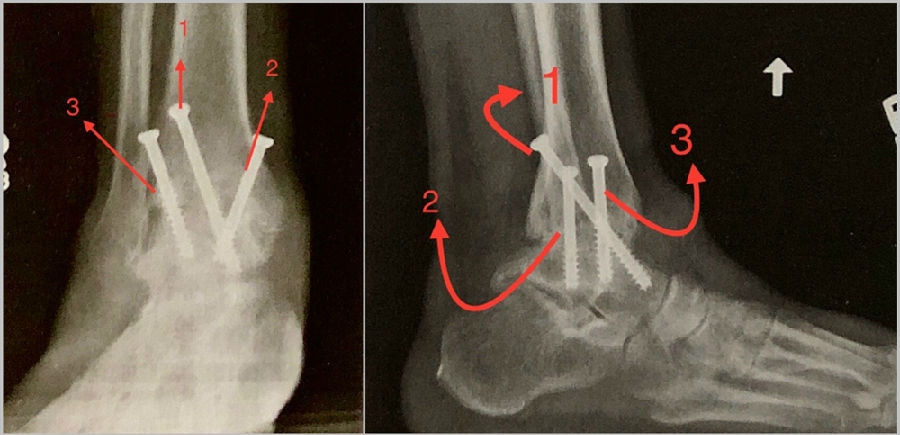

③固定

1枚螺钉自内踝后侧向前下方向打入距骨头颈部;

2枚螺钉自前内踝斜向下至距骨体部;

3枚螺钉自胫骨远端前外侧向距骨体后内侧。

固定方法:

病例报告之二,xx,男,56岁,左踝创伤性关节炎。左踝崴伤6年,疼痛加剧3年。切口显露同前。

23 手术后资料